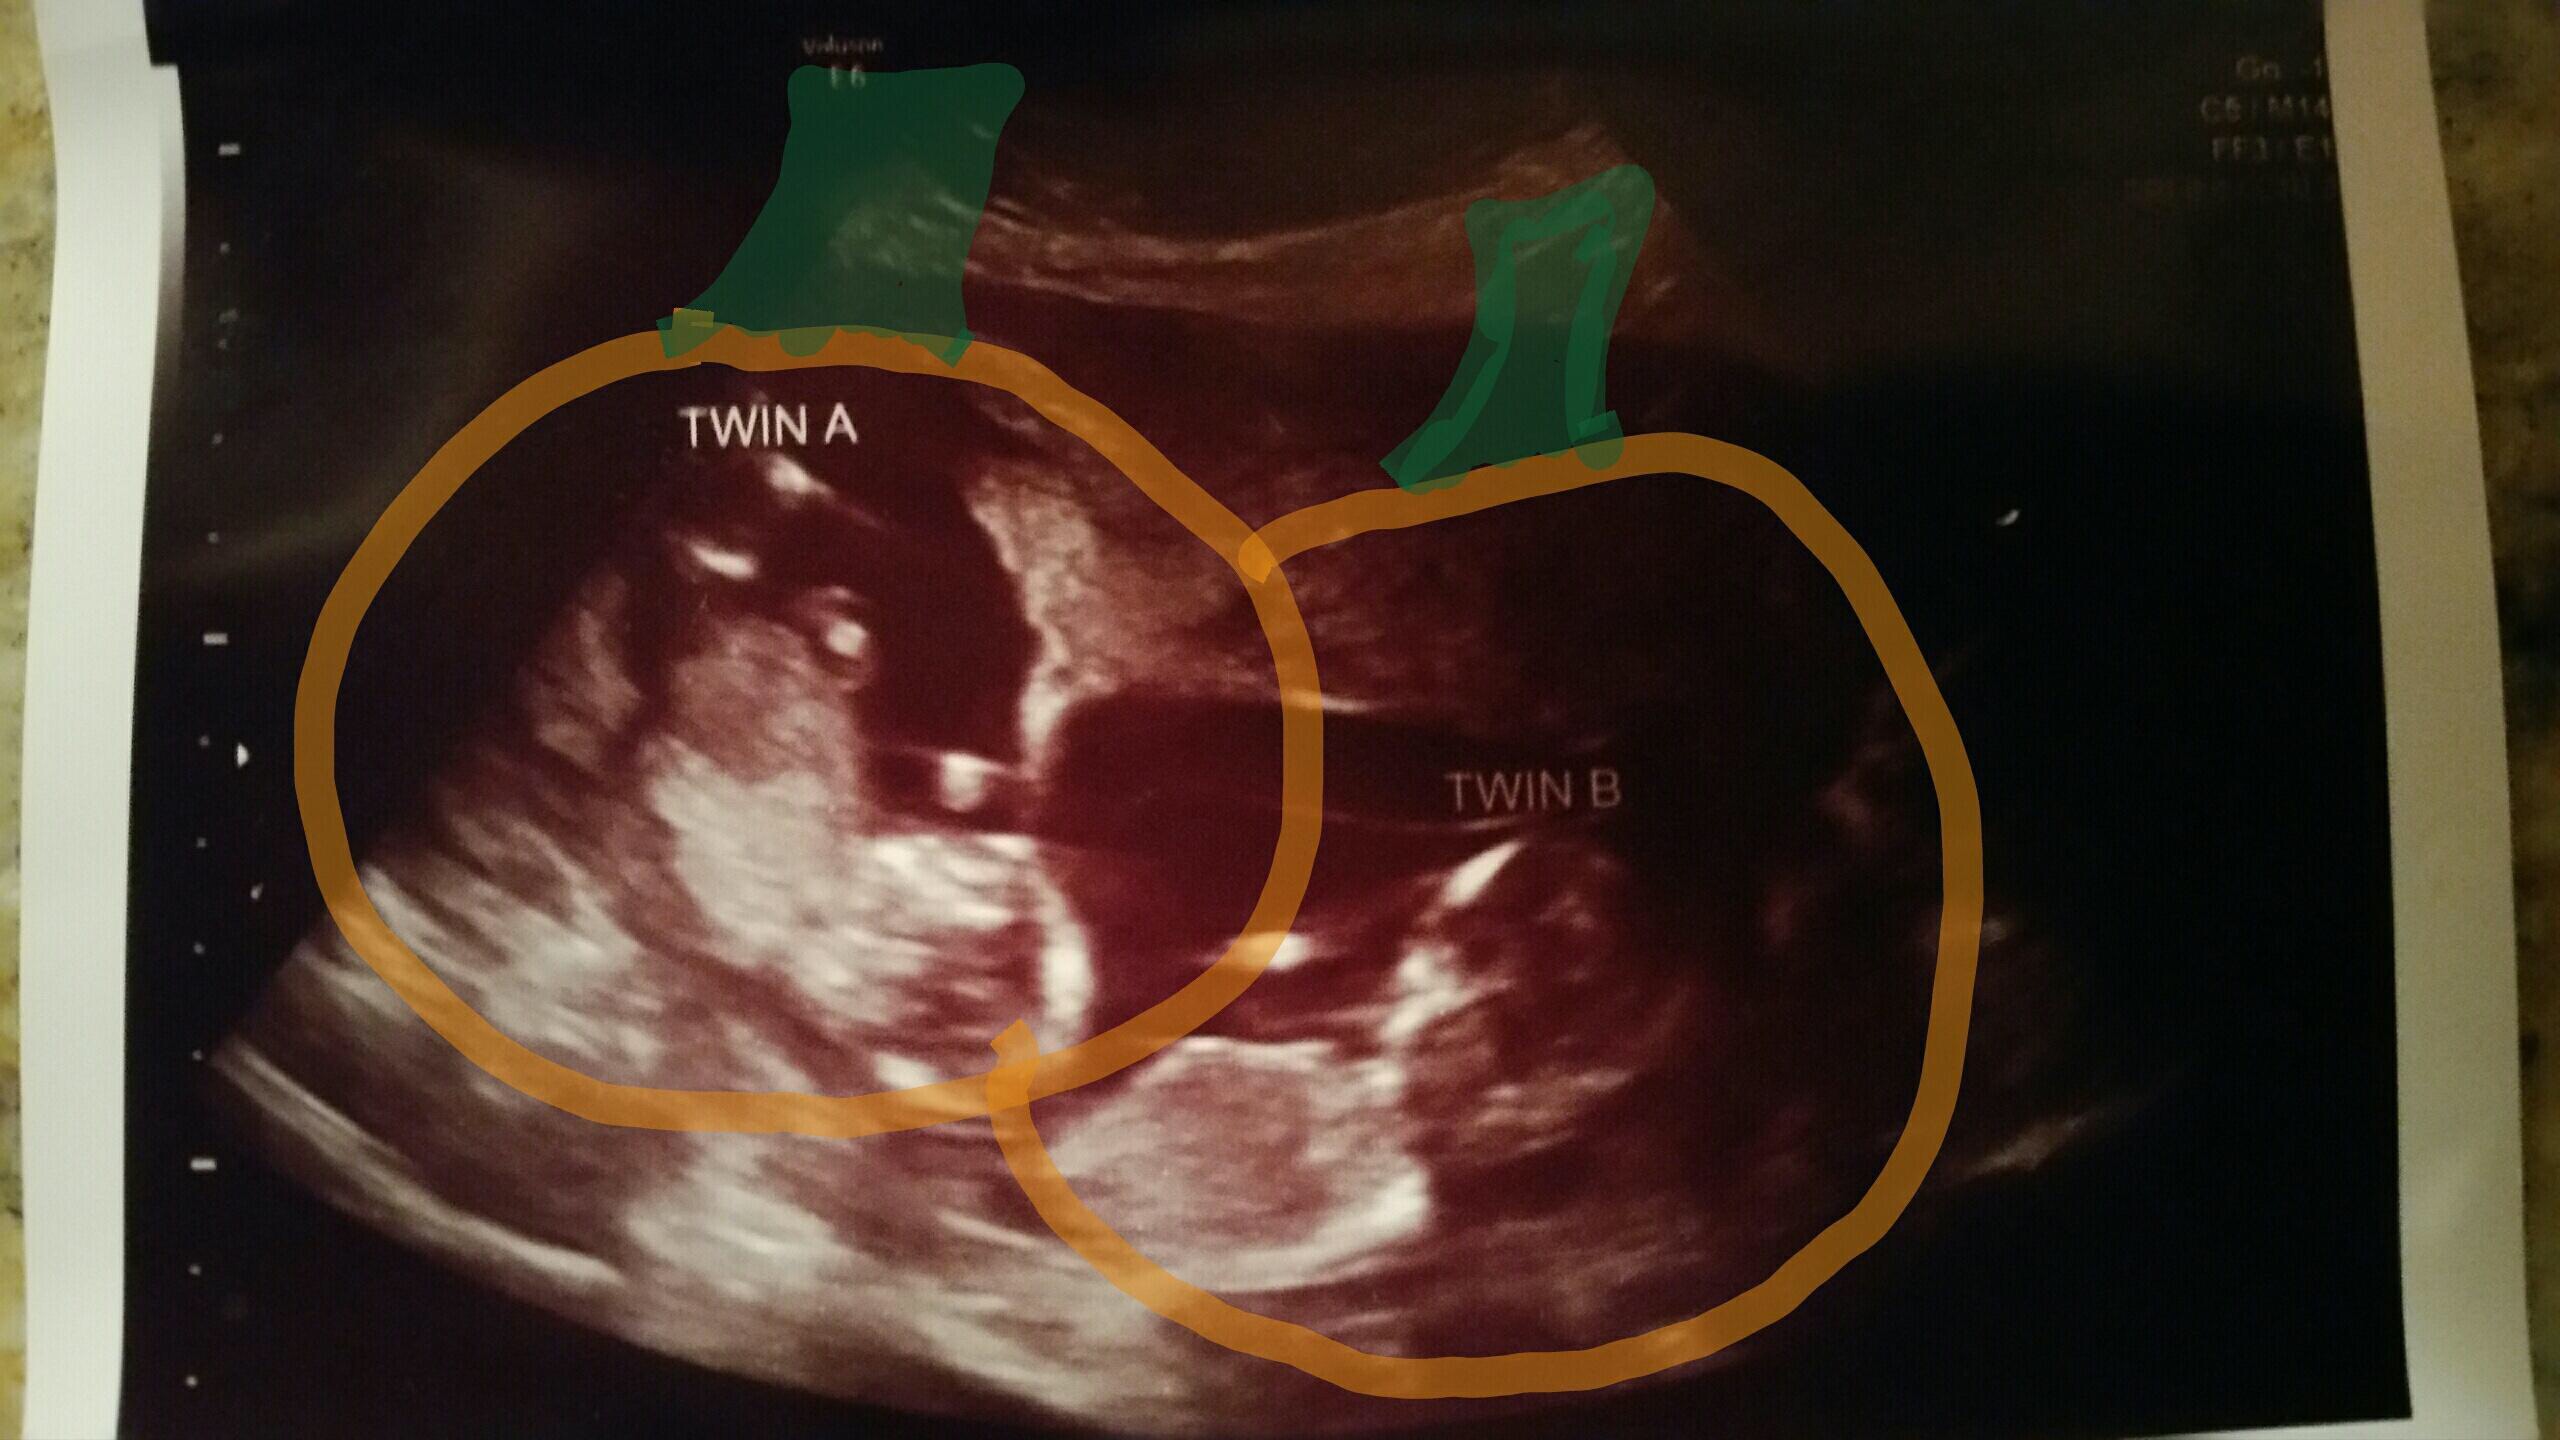

Three weeks ago, baby was measuring a day behind... I'm 11 weeks along today, but baby is now measuring 12 weeks. It was so amazing to watch the little one moving around, waving its arms, and we even got a picture when it was playing with its feet!

We had our second ultrasound last week when I was 11+3. Still measuring a bit bigger, she said I looked about 12 weeks during the scan. Everything looks healthy! Look at that little nose and lips!!!! So in love.